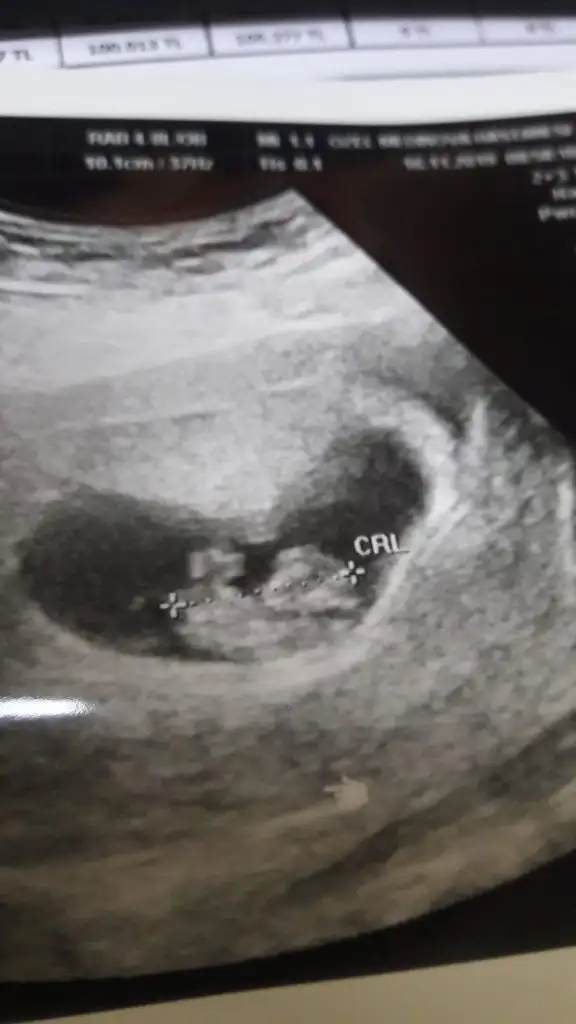

Banada tahmin yaparmısınız ?

• 2C1459C5-D972-419B-A627-FE8068C21191.webp

2C1459C5-D972-419B-A627-FE8068C21191.webp

14,1 KB · Görüntüleme: 54